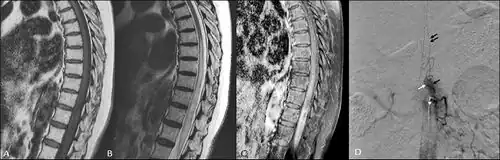

| T2 weighted MRI showing an arteriovenous malformation indicated by the cursor | |

Clinically, the patient may present with neurological symptoms such as numbness, weakness, loss of reflexes, or even sudden or progressive paralysis.[6] The affected portion of the body will correlate to where the lesion lies within the spinal cord. The disease typically has an insidious onset, but symptoms may manifest suddenly. A thorough physical exam may lead a physician toward targeted imaging, with MRI being the most appropriate imaging modality for initial diagnosis. A spinal MRA will serve as a superior imaging technique to visualize the extent of the arteriovenous malformation within the cord and may be especially useful if surgical treatment is attempted.[7]